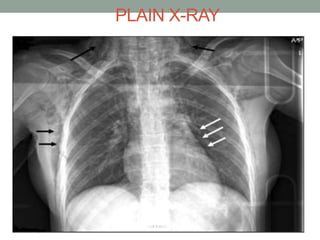

PLAIN X-RAY